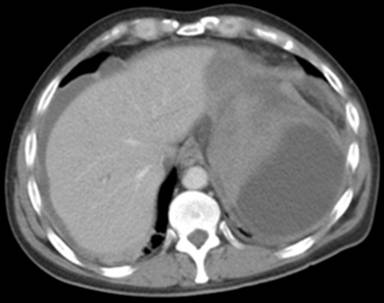

A 47-year-old man with known alcoholic pancreatitis for 10 years was admitted as an emergency with a twenty hour history of left upper quadrant pain radiating to his left shoulder. He was apyrexial and haemodynamically stable. His serum amylase was 245 U/L (reference range: 0-100 U/L) and the white cell count was 17.5 x109/L (reference range: 4-11 x109/L). A CT scan (Figure 1) showed a large sub-capsular fluid collection in his spleen. Twenty four hours later, he suddenly complained of worsening pain and became hypotensive. An urgent CT scan confirmed active bleeding with disruption of the sub-capsular splenic haematoma (Figure 2).

Figure 2. Bleeding due to rupture of the sub-capsular splenic haematoma (Case #1). |

He underwent an emergency laparotomy and at operation was found to have haemoperitoneum from rupture of his splenic sub-capsular haematoma. He underwent a splenectomy and had an uncomplicated postoperative recovery.